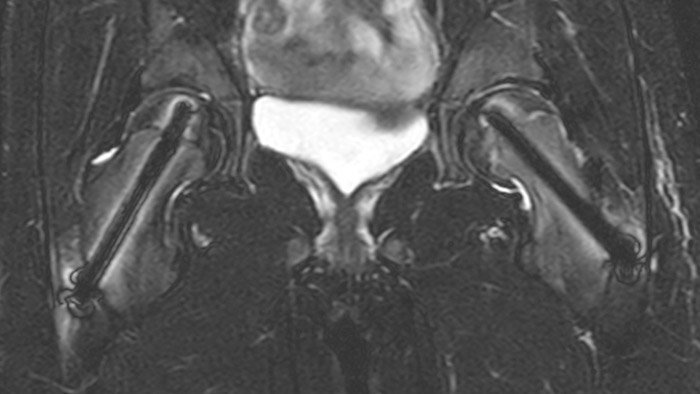

Perthes disease in left hip

The affected area on the upper circumference of the left hip shows contrast uptake in the dynamic scan. The radial scan nicely depicts the hip area, despite the dark shape in the center that is inherent to the radial way of scanning.